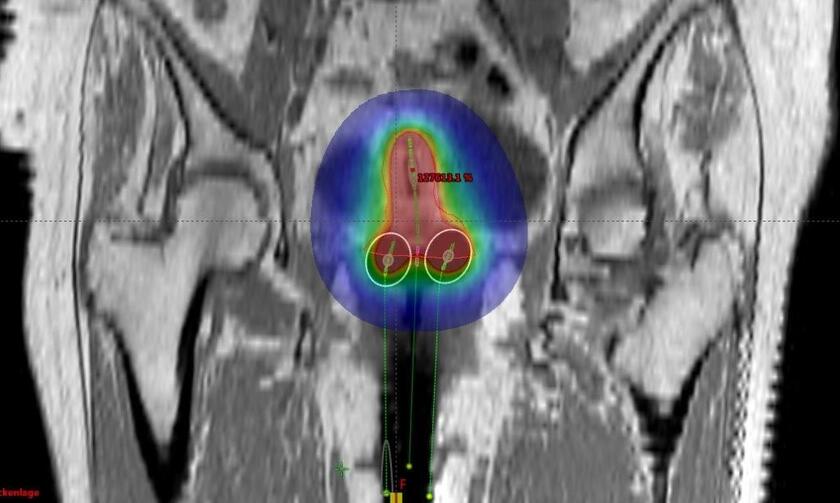

Bestrahlungsplan in Bauchlage für einen Patienten mit Enddarmkrebs.

Bei Patienten mit Enddarmkrebs (Rektumkarzinom) führen wir die Bestrahlung in Rückenlage oder in Bauchlage durch. Das heißt, für den Patienten wird ein Bestrahlungsplan für beide Lagerungen erstellt. Anschließend wird mit dem Behandlungsplan bestrahlt, mit dem eine bessere Schonung von Harnblase und Dünndarm gewährleistet werden kann.